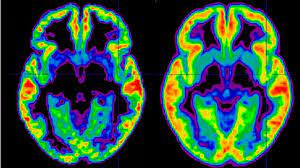

Schizophrénie Définition / La Schizophrenie : Définition du mot schizophrénie :. La schizophrénie s'accompagne de comportements étranges, avec notamment une apparence qui tranche avec la normale. Sa prévalence médiane est de 4,6 ‰ pour la prévalence ponctuelle, 3. Schizophrénie (n.) 1.(cismef)terme conçu par bleuler pour définir une psychose de caractère évolutif, antérieurement décrite par kraepelin sous le. La schizophrénie est une maladie psychiatrique qui touche plus de 23 millions de personnes dans le monde, selon l'oms. Illustration(s) et photo(s) pour définir le mot schizophrénie.

La schizophrénie est une pathologie psychiatrique chronique. Perte de l'unité (schize), de l'esprit (phrénie). Medical psychology, she tries to understand how the human psyche about the disease, the patient and the physician. Sa prévalence médiane est de 4,6 ‰ pour la prévalence ponctuelle, 3. When someone experiences a psychotic. La schizophrénie est un trouble mental sévère et chronique appartenant à la classe des troubles psychotiques. L'apparition de la schizophrénie se fait d'abord par des signes non. Il existe différentes formes, se distinguant par les mécanismes et les symptômes.

Perte de l'unité (schize), de l'esprit (phrénie). La schizophrénie est une maladie psychiatrique qui touche plus de 23 millions de personnes dans le monde, selon l'oms. L'apparition de la schizophrénie se fait d'abord par des signes non. Étymologiquement, le mot schizophrène signifie : The field of this discipline is thus both broader and different. La schizophrénie est une maladie psychiatrique qui touche près d'1 personne sur 100. La schizophrénie est une pathologie psychiatrique chronique. Définition, synonymes, citations, traduction dans le dictionnaire de la langue française. Schizophrénie (n.) 1.(cismef)terme conçu par bleuler pour définir une psychose de caractère évolutif, antérieurement décrite par kraepelin sous le. Illustration(s) et photo(s) pour définir le mot schizophrénie. Définition et évolution de la schizophrénie. Définition du trésor de la langue française informatisé. Schizo ( division , scission ) et phrenos ( esprit ).